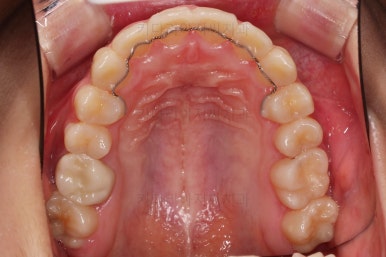

치료 마무리 사진입니다.

불안불안했던 임시치아가 드디어 탈이 났네요.

교정치료를 종료했기 때문에 이제 튼튼한 재료로 크라운치료를 하고 마무리 합니다.

연산동치과 전후사진을 비교해 볼게요.

치열이 가지런해지고 교합도 좋아지고 웃는 모습도 매우 좋아졌네요.

비발치 덧니교정이었지만 입이 튀어나오거나 하지 않고 오히려 치아 각도나 입매가 약간 디ㅜ로 들어가면서 입매도 자연스러워졌어요.

충치치아도 깨끗한 치료가 되었고요.